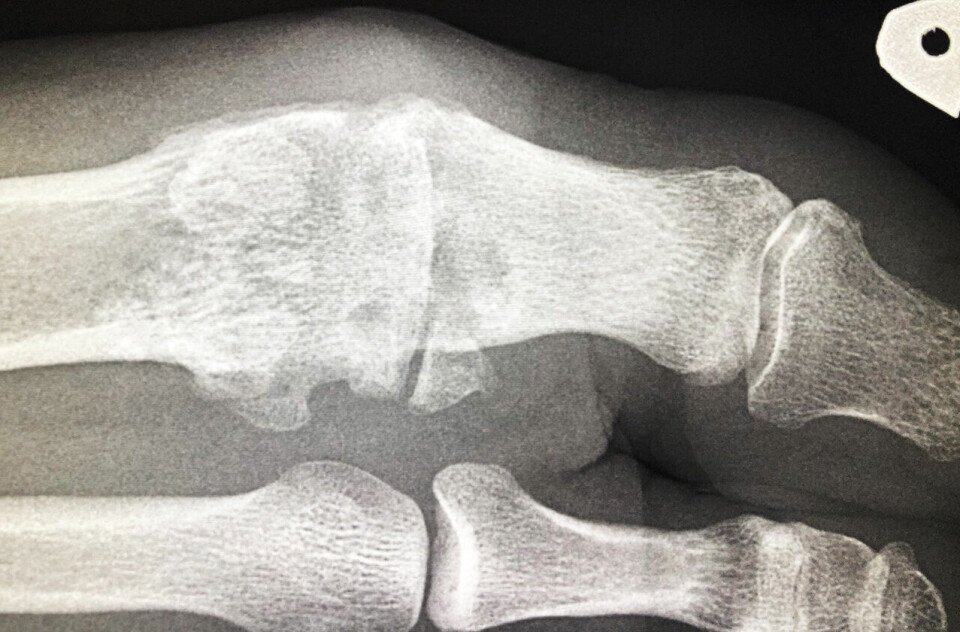

Jeg har nylig tatt røntgen av tåa, og leddet er nedslitt med mye forkalkninger. Fastlegen min anbefaler å stive av grunnleddet ved en operasjon, såkalt artrodese. Han mener at dette greit kan la seg kombinere med løping. Jeg er skeptisk og litt bekymret for ikke å kunne løpe mer. Jeg er i 40-årene og vil gjerne holde på med idrett en stund til.

I en del tilfeller der slitasjen har økt, kan det løsne biter som forkalkes. Det siste er godt synlig på et vanlig røntgenbilde. Brusken derimot vises ikke, da den ikke er røntgentett.

I utredingen av slike tilfeller er røntgen viktig. MR har liten plass og gir dårlig oversikt over det som foreligger.